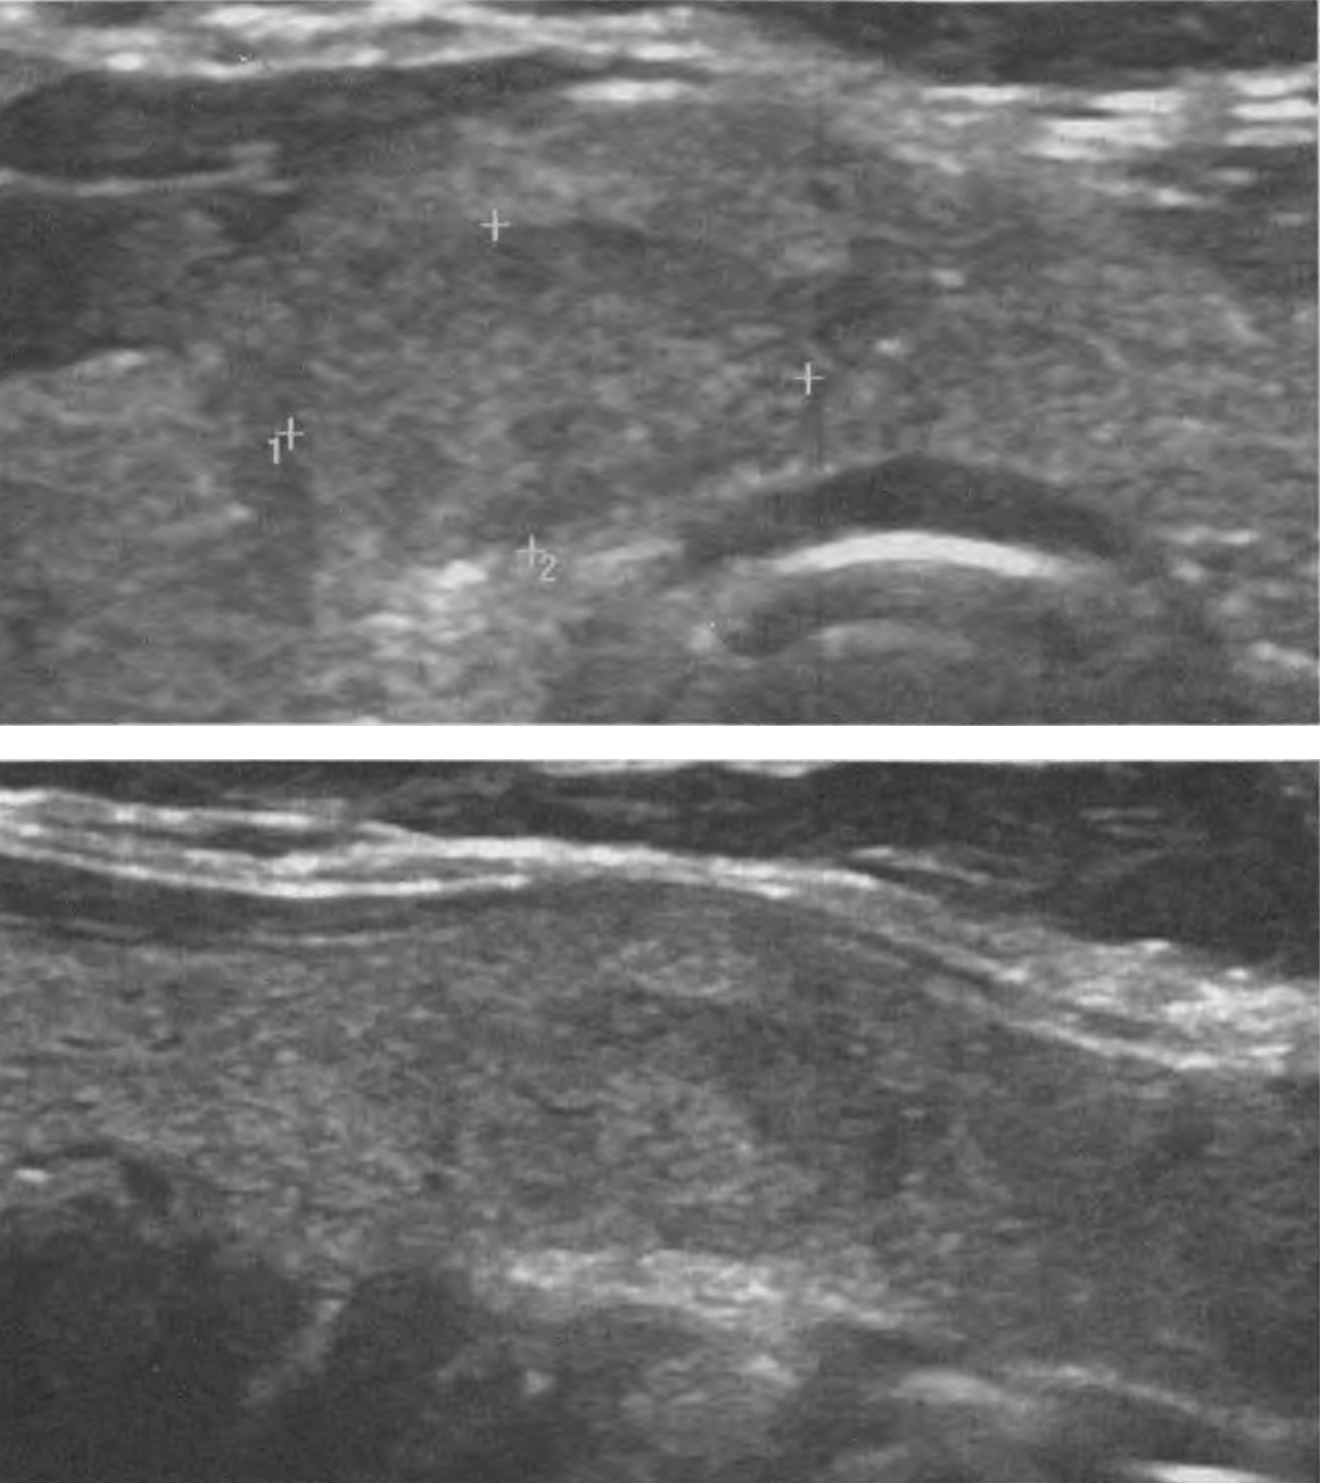

Рисунок 28. Узел 11х6, 4х12,1 мм правой части перешейка ЩЖ у пациентки 44 лет. Тканевой (2 балла); почти изоэхогенный (1 балл); продольное расположение (0 баллов); равномерная граница по большей части периметра (0 баллов); включений нет (0 баллов). Сумма баллов 3, что соответствует 3 уровню ACR TI-RADS. Обратите внимание на чёткие сегменты узловой ткани, подобные по структуре внеузловым долькам – признак доброкачественности (впервые представлен нашей Клиникой).

Рисунок 30. Узел 11,1х6, 8х10,5 мм левой доли ЩЖ у пациентки 67 лет. Тканевой (2 балла), изоэхогенный (1 балл); продольное расположение (0 баллов); равномерная граница по большей части периметра (0 баллов); включений нет (0 баллов); Сумма баллов 3, что соответствует 3 уровню ACR TI-RADS. Этот узел является пролиферативно-гиперпластическим, как результат избыточной внутридольковой регенерации. По моему мнению и мнению коллег, этот узел абсолютно доброкачественный и должен исходно характеризоваться в первой категории ACR TI-RADS как пролиферативно-регенераторный, с присуждением 0 баллов, прекращением дальнейшей оценки и определением 1 уровня ACR TI-RADS.